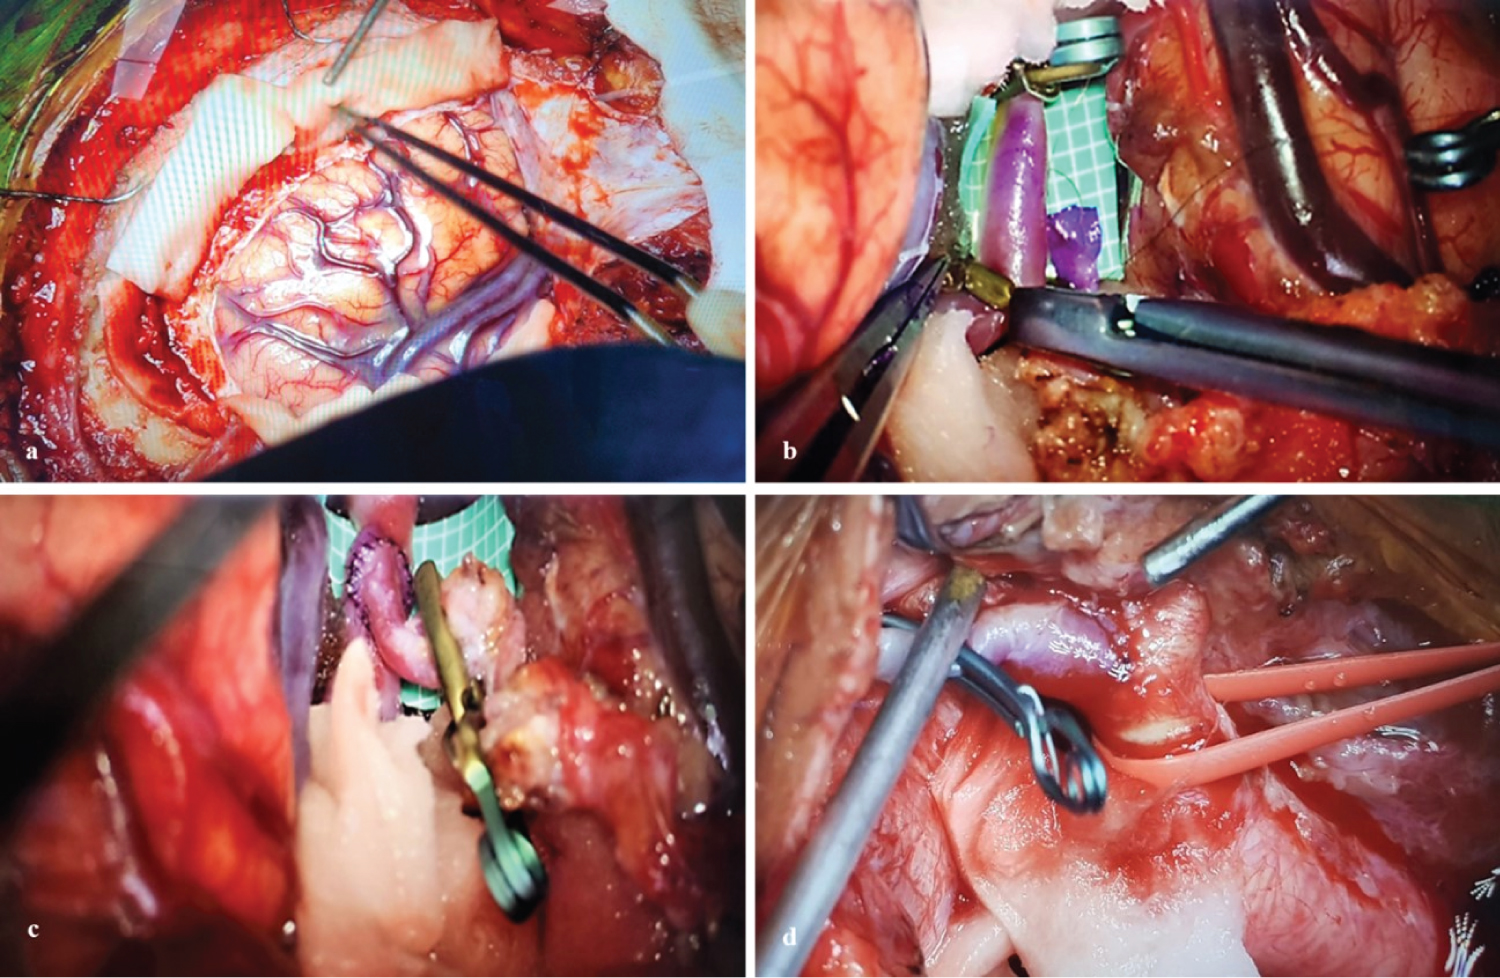

Exposed segment M2 of the middle cerebral artery (MCA), prepares to perform lateral term anastomosis, between the distal branch of the RA graft and segment M2 of the MCA, using a suture with separate points of nylon 10/0. After confirming that there were no leaks in the anastomosis, the radial graft was passed by subcutaneous tunneling under the skin prior to the swallow, avoiding rotation of the graft under the skin and confirmed permeability, temporarily releasing the clip in the graft near the MCA. A smooth, pulsating flow is observed through the non-anastomosed end of the graft. Another cervical proximal lateral term anastomosis is performed between the RA graft and the ACE. Subsequently, a definitive clip is placed at the proximal base of the aneurysm in the cervical ICH, again the vascular patency and anastomosis is corroborated by direct observation of the flow, microvascular Doppler and video angiography with sodium fluorescein, standard methods to corroborate the adequate patency of the graft and exclusion of the ICA and aneurysm (Figure 3).

Figure 3: a) Right frontotemporal craniotomy with approach to the Silvian valley; b,c) Lateral term anastomosis between distal M2 - RA; d) Dissection and preparation ACE where distal anastomosis will be performed AR-ACE. View Figure 3